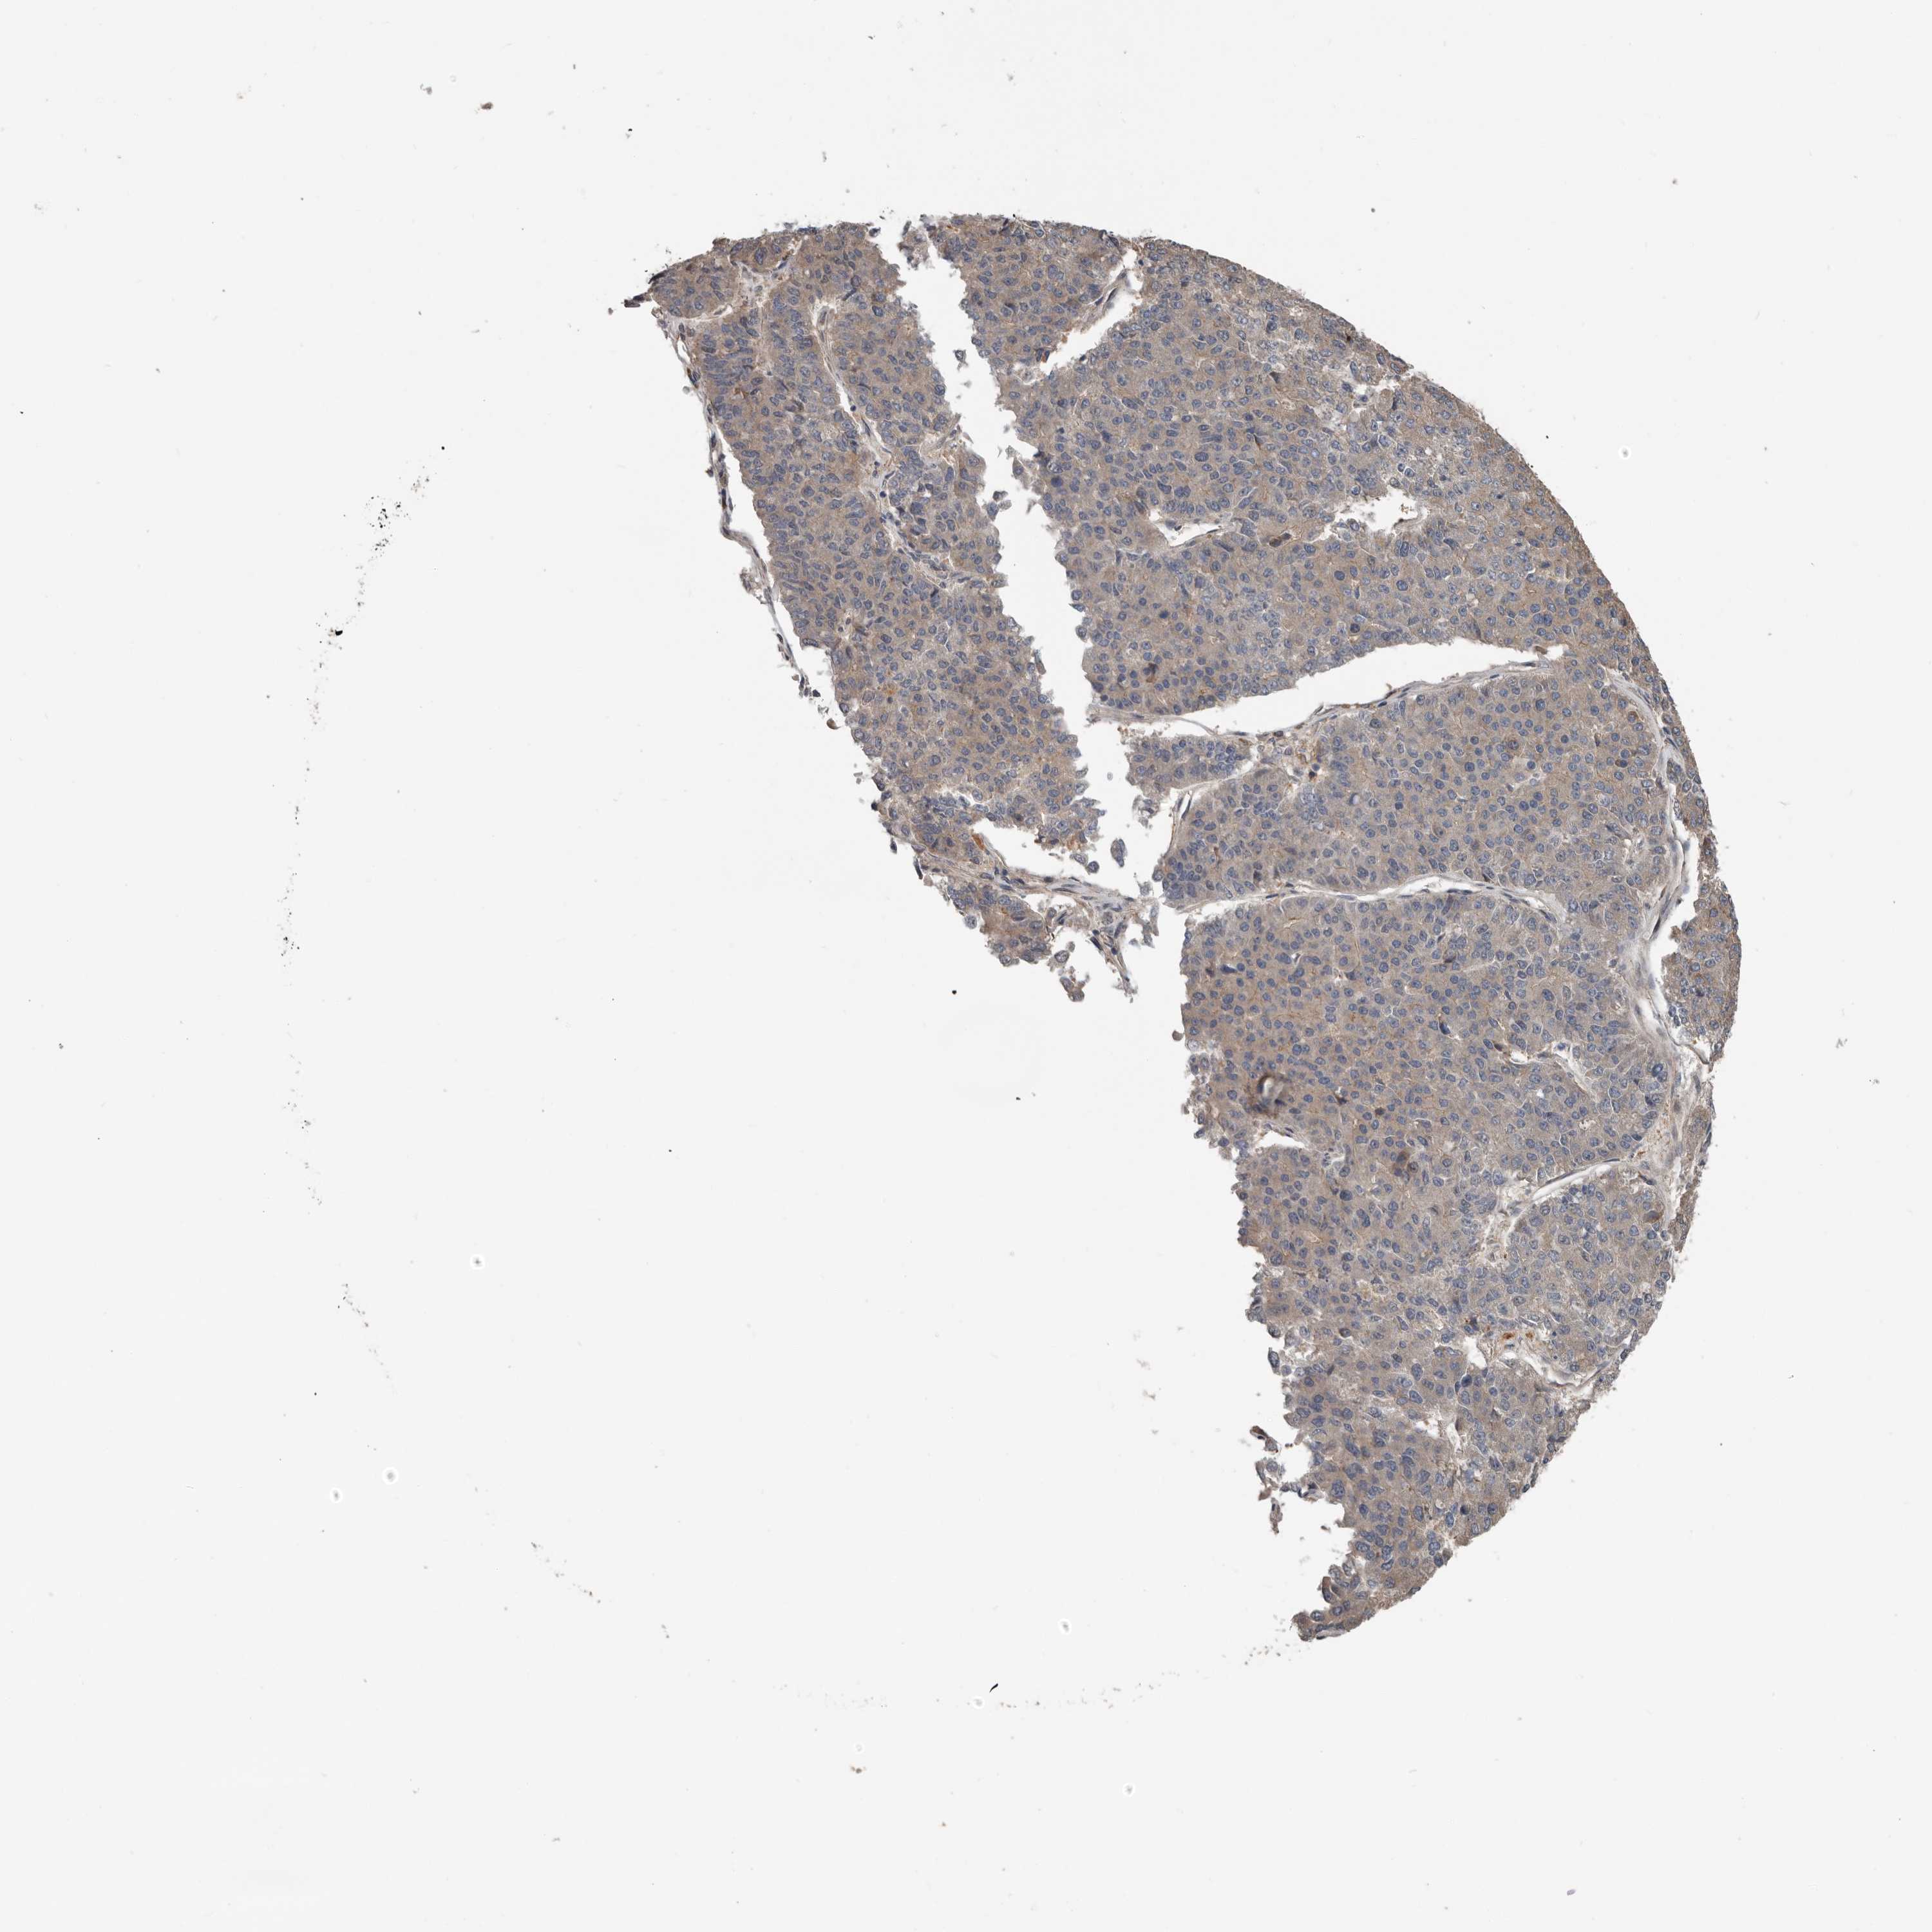

PANCREATIC CANCER - Protein expressioni

A mouse-over function shows sample information and annotation data. Click on an image to view it in a full screen mode. Samples can be filtered based on level of antibody staining by selecting one or several of the following categories: high, medium, low and not detected. The assay and annotation is described here.

Note that samples used for immunohistochemistry by the Human Protein Atlas do not correspond to samples in the TCGA dataset.

Antibody stainingi

Antibody staining in the annotated cell types in the current human tissue is reported as not detected, low, medium, or high, based on conventional immunohistochemistry profiling in selected tissues. This score is based on the combination of the staining intensity and fraction of stained cells.

Each image is clickable and will lead to virtual microscopy that enables deeper exploration of all samples and also displays staining intensity scores, fraction scores and subcellular localization as well as patient and tissue information for each sample.

Antibody HPA028400

Antibody HPA028439

Staining

High

Medium

Low

Not detected

Intensity

Strong

Moderate

Weak

Negative

Quantity

>75%

75%-25%

<25%

None

Location

Nuclear

Cytoplasmic/membranous

Cytoplasmic/membranous,nuclear

Adenocarcinoma, NOS